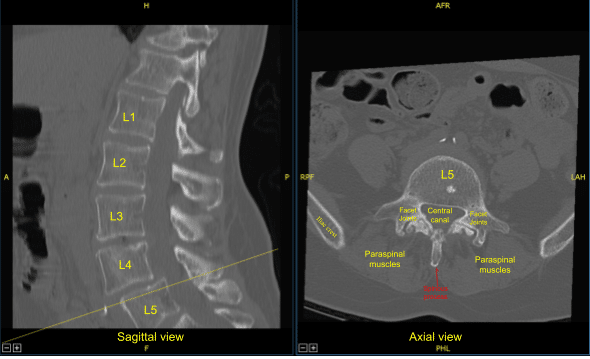

Preoperative CT of Lumbar Spine

Prior physical examination of the lumbar spine supported the diagnosis of lumbar canal stenosis. His imaging showed grade 1 to grade 2 spondylolisthesis with instability over L4-L5 with compression of nerve roots. There is also lateral recess compression at L3-L4 on the right and left side with compression of the traversing L4 nerve root.